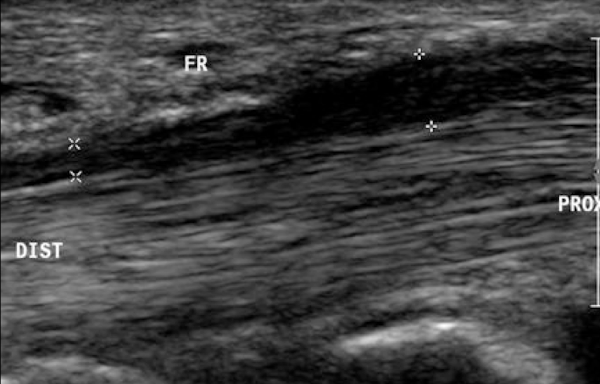

USG SxTC

Excelente metodo

aplanamiento del nervio-hipoecoico

engrosamiento del retinaculo

detección de masas o quistes